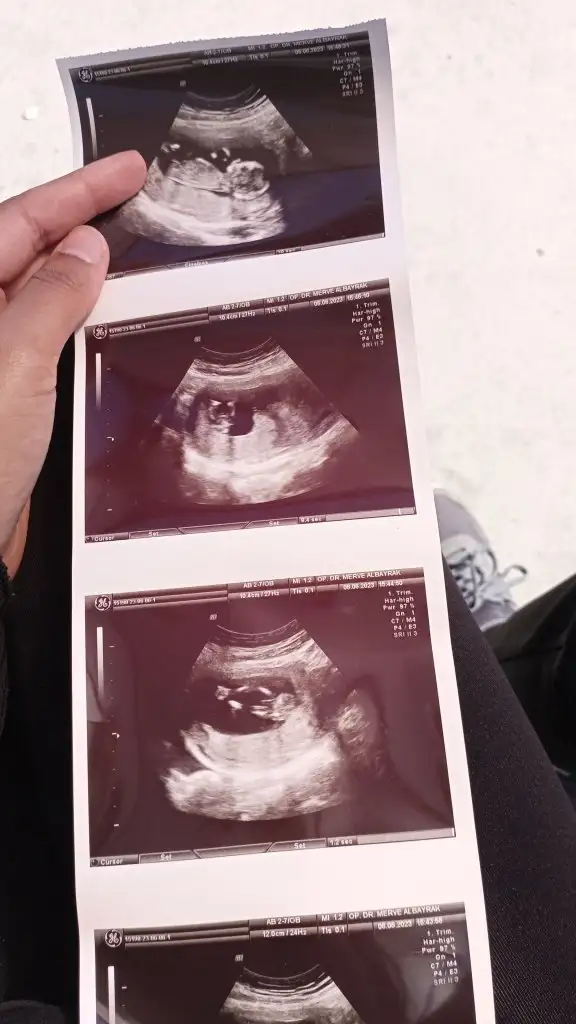

Meraba kızlar 13 haftalık ultrson resmi doktor mınık çıkıntı gördüğünü söyledi fakat çıkıntı üzüntü değil dedı gölge var dedı net ne kız nede net erkek dedı sadece erkek olabilir 1-2 hafta sonra net bellı olcak bırde siz balar mısınınz çok heyecanlıyım:) ıkılı test ıcın ense kalınlığna bakılınca orda çıkıntı yok kız dediler kafam çok karıstı

Valla bende esımde oğlum da kız hissediyoruz radyoloji uzmanı ense ölcüsü kız dedı çıkıntı sivri değil minik dedı erkek olsa 13 de sivri belirgin çıkıntı olur dedı bızım doktor emin olamadı sadece tahminde bulundu pazarteai gidicem inşallah net kız oldğu çıkar dedğinz gibi aay çok heyecanladnım:)